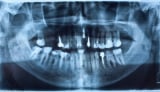

Digitální RTG diagnostika

Pro ověření nálezu používáme digitální rentgeny, které odhalí skryté kazy v mezizubních prostorech nebo záněty v kosti, které nejsou viditelné pouhým okem.